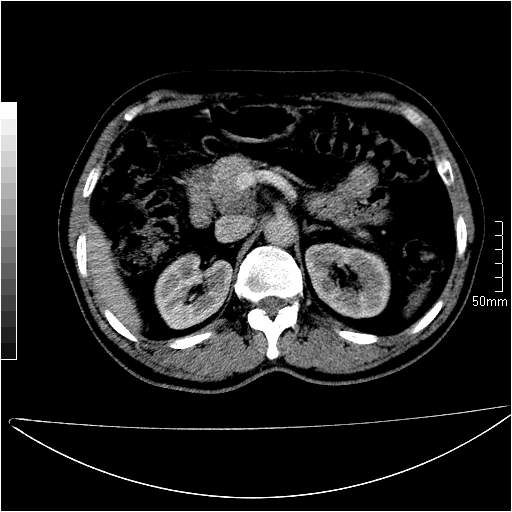

男性,54岁,皮肤黄染,搔痒一周余.b超示肝左叶回声异常.初步诊断1胆总管下段结石2胆囊结石伴慢性胆囊炎请各位战友帮忙看一下肝脏多发低密度如何解释恰当.增强效果不是很好.请大家见谅.

胆总管及肝内胆管扩张,考虑是结石!但,肝内的低密度区增强不明,可能是肝ca,因为肝ca在增强时呈快进快出.另年胆总管扩张原因,可以考虑一下是不是,胆管ca.再次要考虑肝内的低密度是否为海绵状血管瘤所致!

首先,胆总管下端结石梗阻伴肝内胆管扩张可确定。

其次,增强动脉期肝静脉显影,肝实质密度不均。——此为右心功能不全引起肝淤血的表现。

另外,肝八段低密度占位,呈多灶性,考虑肝脓肿或肝癌可能,(图像质量欠佳)建议进一步检查。

由于胆囊窝内结构显示不清,肝脏病灶又邻近胆囊窝首先考虑胆囊癌肝受侵犯。而后因肝脏病灶强化有渐进改变,且相邻胆管扩张,故考虑肝胆管细胞癌待排。

左肝胆管细胞癌。

胆总管下端结石。